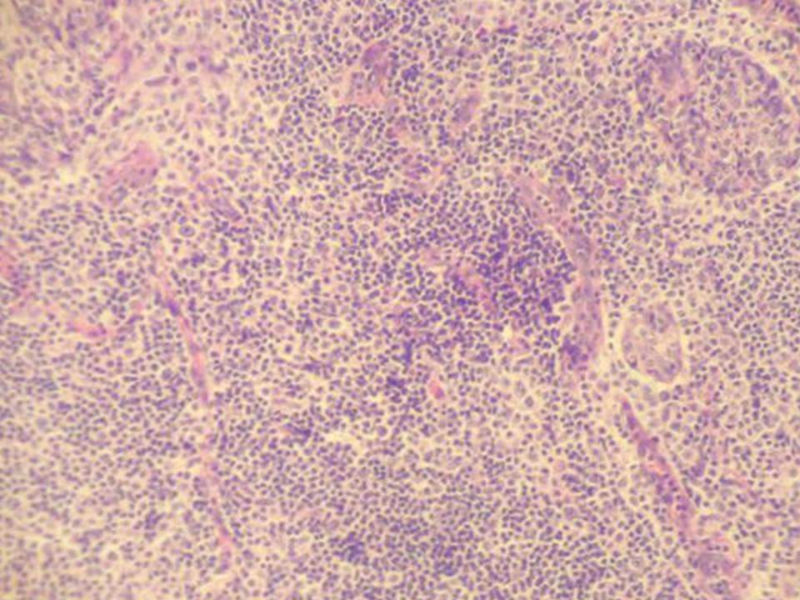

女,71岁,腮腺肿物,临床诊断混合瘤。

图3